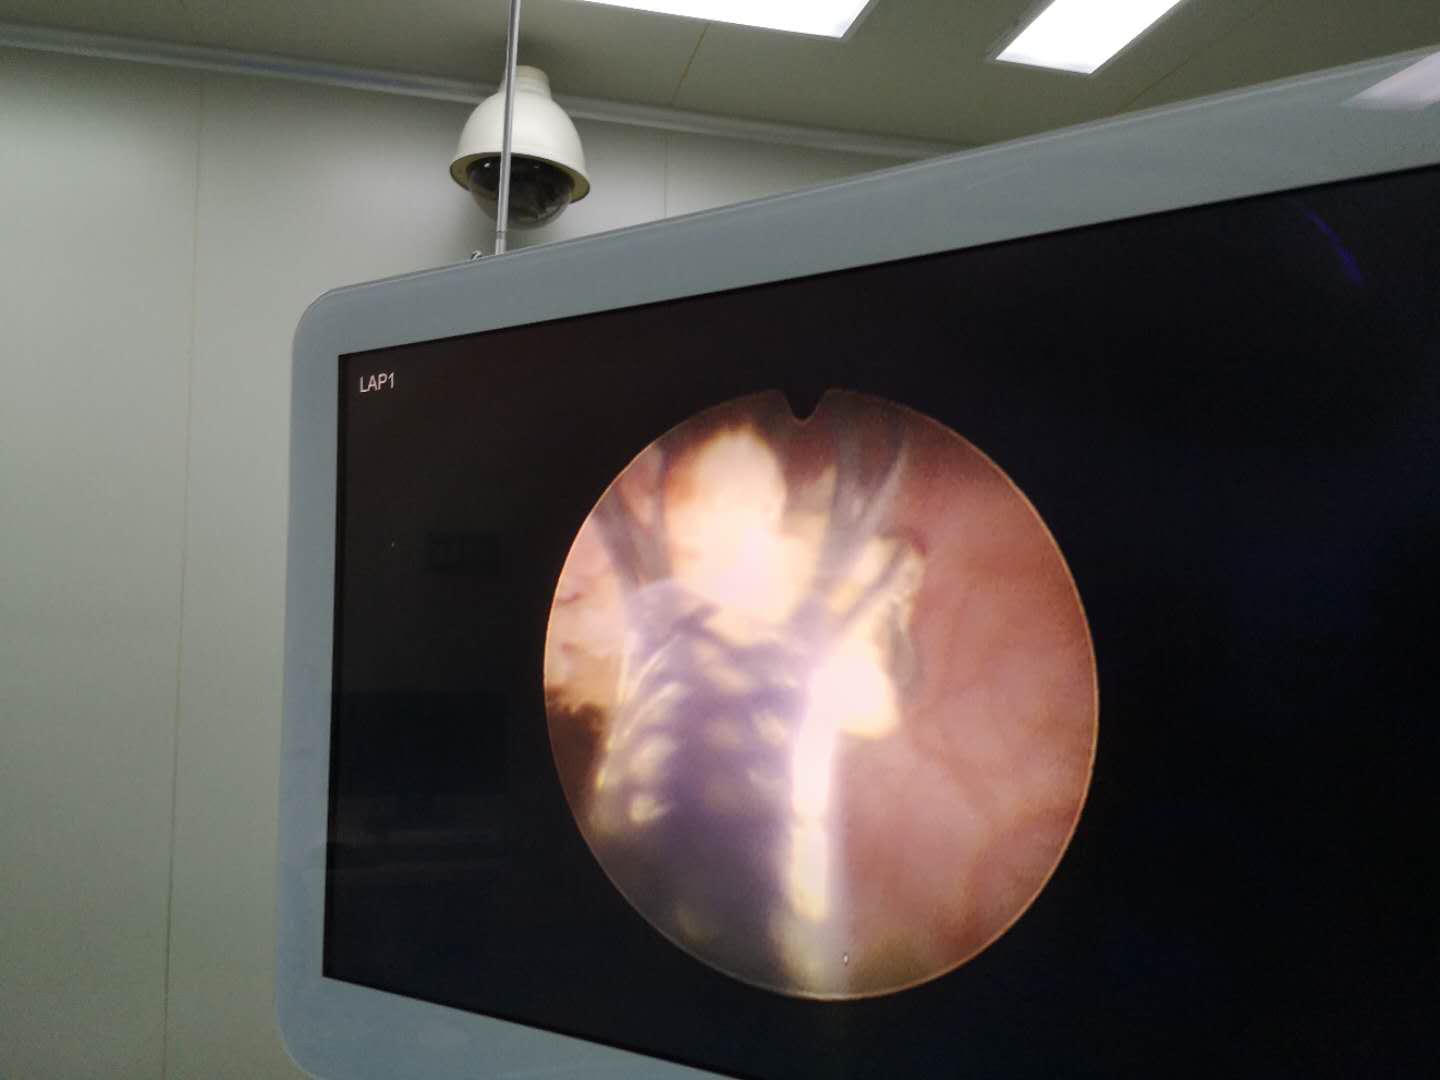

患儿,男,2岁4个月,家住张店洪沟社区,因排尿困难伴疼痛急来医院就诊,经检查确诊为膀胱结石和尿道结石,结石堵塞尿道导致患儿小便时急得满头大汗也排不出来,排出少许还是血尿。医师李鹏在全麻状态小儿膀胱镜下采用钬激光碎石,顺利将结石粉末化后冲洗至体外,手术成功并且患儿无不适。

输尿管软镜钬激光取石术是目前国内外新的手术方法,采用世界的纤维输尿管软镜及碎石设备钬激光由人体自然尿道,直达肾脏(肾盂内)或肾盏部位找到结石,将结石击碎,使其随尿液自行排出体外。

可控可视、高新科技:钬激光光纤是可弯曲的,可以通过软性输尿管镜等导入,对泌尿系的任何部位结石均可进行可视化有效碎石。